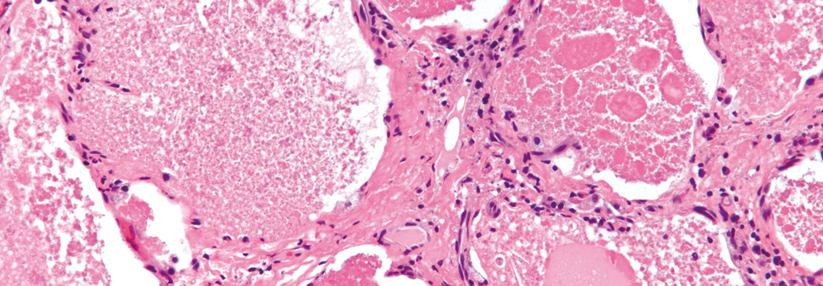

Die pulmonale Alveolarproteinose (PAP) zählt zu den seltenen Atemwegserkrankungen. Typisches Kennzeichen ist eine stetig zunehmende Ansammlung von Surfactant in den Alveolen. Je nach Pathomechanismus wird die Erkrankung in verschiedene Formen eingeteilt: